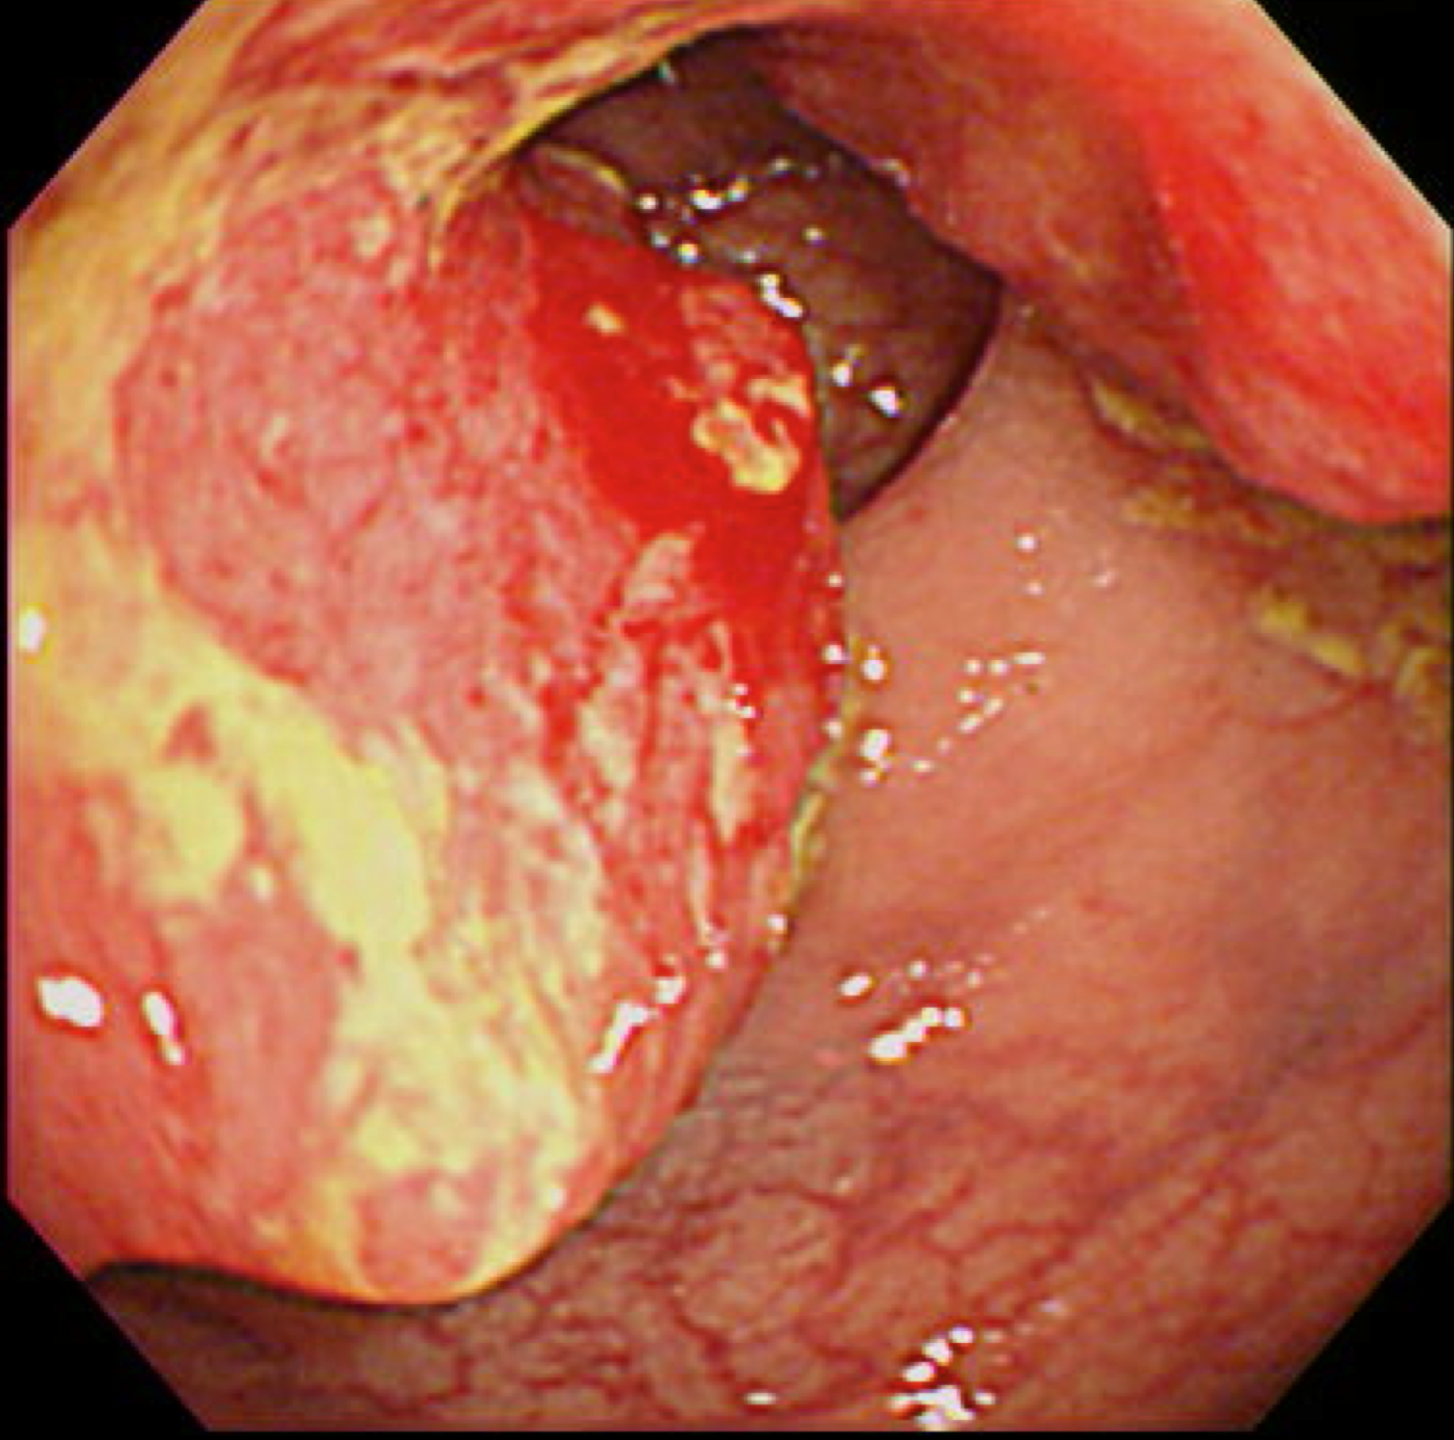

大腸がん(S状結腸癌)

大腸がん検診

写真は過去に当院でおこなった大腸内視鏡で発見された癌ですが、現在は当院では大腸内視鏡をおこなっておりません。そのため検査をおこなう医療機関へ紹介させていただきます。